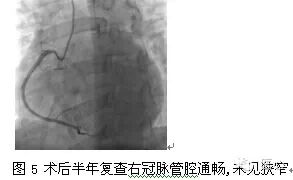

出院后规律服药,但仍反复活动时心前区憋闷疼痛,向左肩背部放射,伴发力气短,每次持续10余分钟至半小时,经休息可缓解。支架术后半年时冠脉造影复查。冠脉造影示:右冠管腔通畅,未见狭窄,TIMI血流3级(图5);左冠脉原支架通畅,可见明显弥漫瘤样扩张,以前降支近中段为主,TIMI血流3级(图3、图4)。术后予以继续前述药物治疗方案,瞩终身服用阿司匹林及华法林。